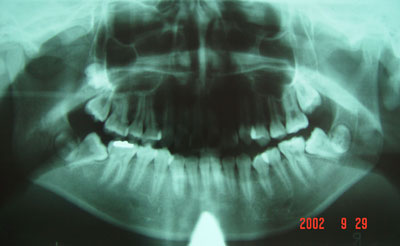

2、固定矫治器 它粘固在牙齿上,可以精确地移动牙齿,能够矫治各种复杂的错合畸形,矫治效果好,是目前国内外最常使用的矫治器。各种固定矫治器大都由带环、矫治弓丝、托槽等三部分组成。我国自从开展固定正畸以来,先后用过Begg细丝弓矫治器、方丝弓矫治器、直丝弓矫治器来矫治错合畸形。目前国内普遍采用的是直丝弓矫治器。按照直丝弓托槽的槽沟角度的不同设计,常用的直丝弓矫治器又可分为Roth系列直丝弓矫治器、OPA-K直丝弓矫治器、MBT直丝弓矫治器等。按照托槽所用材质的不同,可以分为国产金属托槽、进口金属托槽、生物陶瓷托槽。